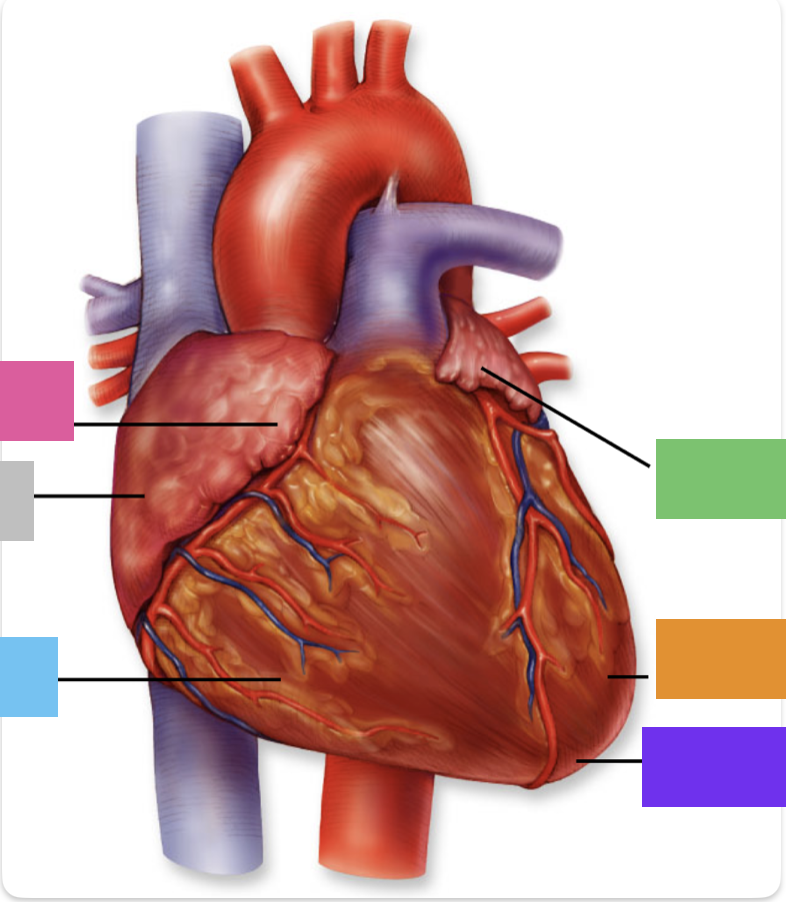

light purple

base

purple

apex

grey

right atrium

pink

right auricle

green

left atrium

green

left auricle

blue

right ventricle

orange

left ventricle

green

coronary (atrioventricular) sulcus

pink

interatrial septum

dark blue

interventricular septum

green

anterior interventricular sulcus

green

posterior interventricular sulcus

right coronary artery

posterior interventricular artery

left coronary artery

anterior interventricular artery

circumflex artery